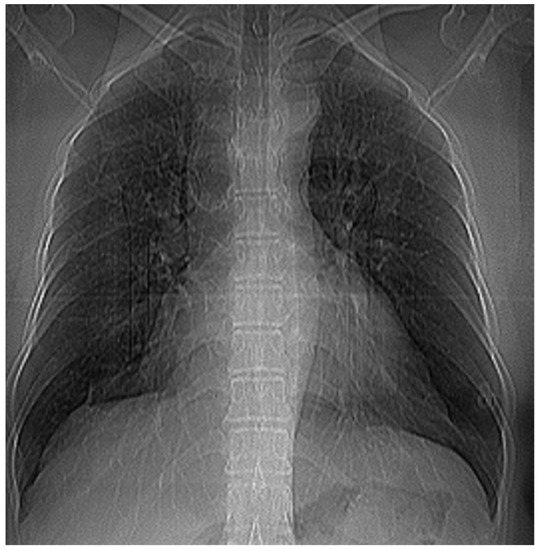

3.7. Results of Healthy Patients—A Final Comparison Using Control Data

In this subsection, we present and discuss the pulmonary CT scan of healthy lungs, which were not affected by the presence of SARS-CoV-2.

The chest radiograph of healthy lungs on which the fractal analysis was performed is shown in Figure 29a. Aside from the high-quality imaging provided by CT procedures (Figure 29a,b), the picture evaluation assured quantitative information regarding various structural features, such as the fractal dimension and lacunarity.

Figure 30 shows the 2D box-counting algorithm with the local fractal dimension calculation for the healthy-lung CT image. Figure 31 displays the 3D graphical representation of the voxels present in the CT lung image of healthy patient. Table 7 presents the calculated values for the fractal dimension and the lacunarity of the CT image evaluations for the healthy patient.

Table 7 shows the known fractal indicators, such as the fractal dimension of the CT image of the left lung, dHL = 1.6410 ± 0.3577, and lacunarity Λ = 0.0475; and the fractal dimension of the right lung, dHR = 1.6318 ± 0.3598, and lacunarity, Λ = 0.0486.